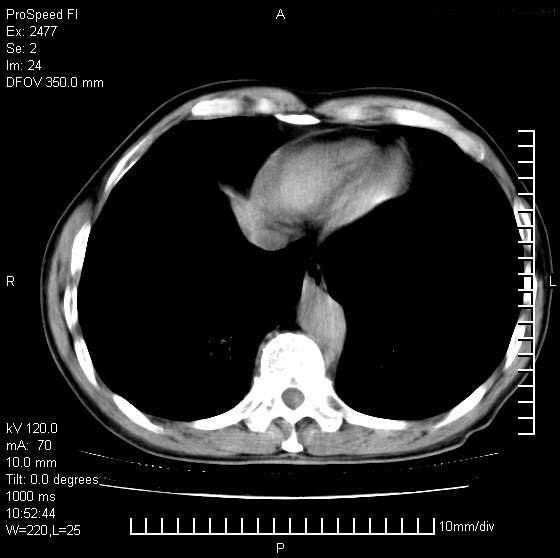

以下是引用天南地北在2007-10-9 14:29:00的发言:[br]1:右上肺结核[br]2:右肺下叶肿块:不支持肺癌,首先考虑炎性病变-肺脓疡可能性大[br]理由:1:临床病史支持,肺脓肿症状不明显应该是不规则服药造成。[br] 2:肿块边缘模糊,周围可见炎性渗出,长毛刺,内见支气管征,不过有点不规则。[br] 我感觉下肺癌这个诊断有点偏左,建议积极抗炎治疗后复查

以下是引用卜一在2007-10-9 15:55:00的发言:[br][br] [br] 1:右上肺结核[br]2:右肺下叶肿块:不支持肺癌,首先考虑炎性病变-肺脓疡可能性大[br]理由:1:临床病史支持,肺脓肿症状不明显应该是不规则服药造成。[br] 2:肿块边缘模糊,周围可见炎性渗出,长毛刺,内见空气支气管征,不过有点不规则。[br] 我感觉下肺癌这个诊断有点偏左,建议积极抗炎治疗后复查![br]支持! [br] [br] [br]

以下是引用wxy7406在2007-10-9 21:02:00的发言:[br]结合临床病史首先考虑感染性病变,但周围型肺癌不能除外,1.患者年龄偏大2.临床有咯血3.(也觉得是最重要的一点)病灶内有偏心性空洞。

以下是引用王仕学在2007-10-9 13:48:00的发言:[br]右下肺周围性肺癌可能性大,最好活检吧

以下是引用hhcckk在2007-10-9 15:18:00的发言:[br]右上肺病灶考虑结核,病灶多种形态并存(纤维化、增殖性病灶并存)[br]右下肺病灶比较难说,个人意见更趋向于“天南地北”的诊断----肺脓肿[br]1、病人有明显的寒战,高热,肿瘤病人很少出现[br]2、病灶周围的肺纹理走向柔和,没有肿瘤病灶常见的集束征[br]3、病灶边缘的毛刺较长,恶性肿瘤多为短毛刺[br]痰中血丝和病人的年龄是两个不利于良性肿块的因素,建议早点活检

以下是引用ydx_74在2007-10-9 15:53:00的发言:[br]右上肺结核,右下中心性肺癌可能大,肺门淋巴结肿大。